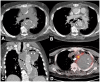

Non-traumatic thoracic aorta emergencies are associated with significant morbidity and mortality. Diseases of the intimomedial layers (aortic dissection and variants) have been grouped under the common term of acute aortic syndrome because they are life-threatening conditions clinically indistinguishable on presentation. Patients with aortic dissection may present with a wide variety of symptoms secondary to the pattern of dissection and end organ malperfusion. Other conditions may be seen in patients with acute symptoms, including ruptured and unstable thoracic aortic aneurysm, iatrogenic or infective pseudoaneurysms, aortic fistula, acute aortic thrombus/occlusive disease, and vasculitis. Imaging plays a pivotal role in the patient's management and care. In the emergency room, chest X-ray is the initial imaging test offering a screening evaluation for alternative common differential diagnoses and a preliminary assessment of the mediastinal dimensions. State-of-the-art multidetector computed tomography angiography (CTA) provides a widely available, rapid, replicable, noninvasive diagnostic imaging with sensitivity approaching 100%. It is an impressive tool in decision-making process with a deep impact on treatment including endovascular or open surgical or conservative treatment. Radiologists must be familiar with the spectrum of these entities to help triage patients appropriately and efficiently. Understanding the imaging findings and proper measurement techniques allow the radiologist to suggest the most appropriate next management step.